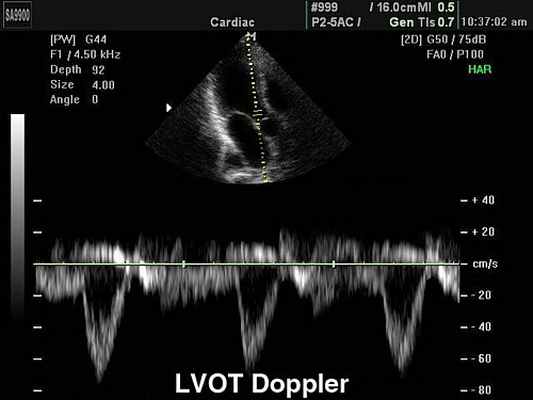

Импульсный допплер (Pulsed Wave, или PW). Графическая разверстка импульсно-волнового допплера отражает характер кровотока в конкретной данной точке, в месте установки контрольного объема. Точка установки контрольного объема называется базовой линией. По вертикали на графике откладывается скорость потока, по горизонтали - время. Все потоки, которые в конкретной данной точке движутся к датчику располагаются на графике выше базовой линии; все потоки, которые движутся от датчика - ниже нулевой линии. Помимо формы и характера кровотока на графике можно зафиксировать щелчки открытия и закрытия створок клапанов, дополнительные сигналы от хорд створок и стенок сердца. Импульсный допплер имеет скоростной предел (не более 2,5 м/с ), поэтому с его помощью нельзя зарегистрировать потоки, имеющие высокую скорость.

Импульсный высокочастотный допплер (HFPW - high frequency pulsed wave). Несколько контрольных объемов распологаются один за другим на различной глубине. Это позволяет регистрировать кровоток, скорость которого превышает 2,5 м/с.

Постоянно-волновой допплер (CW - Continuous Wave Doppler). Позволяет регистрировать высокоскоростные потоки. Недостаток метода состоит в том, что на графике регистрируются все потоки по ходу луча. Методика CW допплеровского исследования позволяет произвести расчеты давления в полостях сердца и магистральных сосудов в ту или иную фазу сердечного цикла, рассчитать степень значимости стеноза и т.д.

Основным уравнением CW является уравнение Бернулли, позволяющее расчитать разницу давления или градиент давления.С помощью уравнения можно измерить разницу давления между камерами в норме и при наличии патологического, высокоскоростного кровотока.